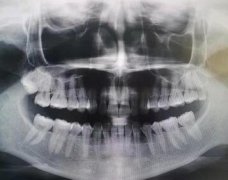

佛山顺德壹加壹周光明做牙齿矫正怎么样?一下我就敢开心的笑了

2022-10-05

佛山曙光口腔陈远高做的牙齿矫正,牙齿的前突状况也有了改善

佛山曙光金子口腔陈远高牙齿矫正做的好吗?

佛山穗华口腔王静做隐形矫正怎么样?透明的矫正器不会疼痛也更加美观

佛山穗华口腔王静医师矫正牙齿果好吗?期待自己的变化